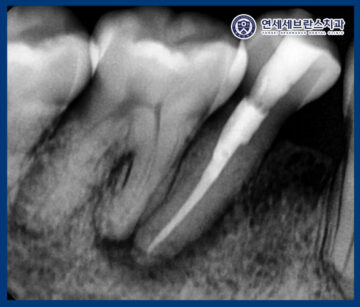

자세한 확인을 위해

엑스레이 사진을 촬영해 보니,

치아 뿌리 끝 염증을

관찰할 수 있었습니다.

치아 속 신경이 살아있는 기능이 소실되어 생기는

전형적인 증상이 나타나

또한 엑스레이 상 뒤쪽 치아까지

염증이 이환된 것으로 보이나,

신경이 살아있는 것으로 확인되어

앞 치아만 진행하고 추후 통증 발생 시

추가로 신경치료를 진행하기로 하였습니다.